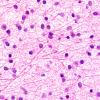

NEOPLASMS (GLIAL)

Astrocytoma, IDH-mutant, WHO Grade 2